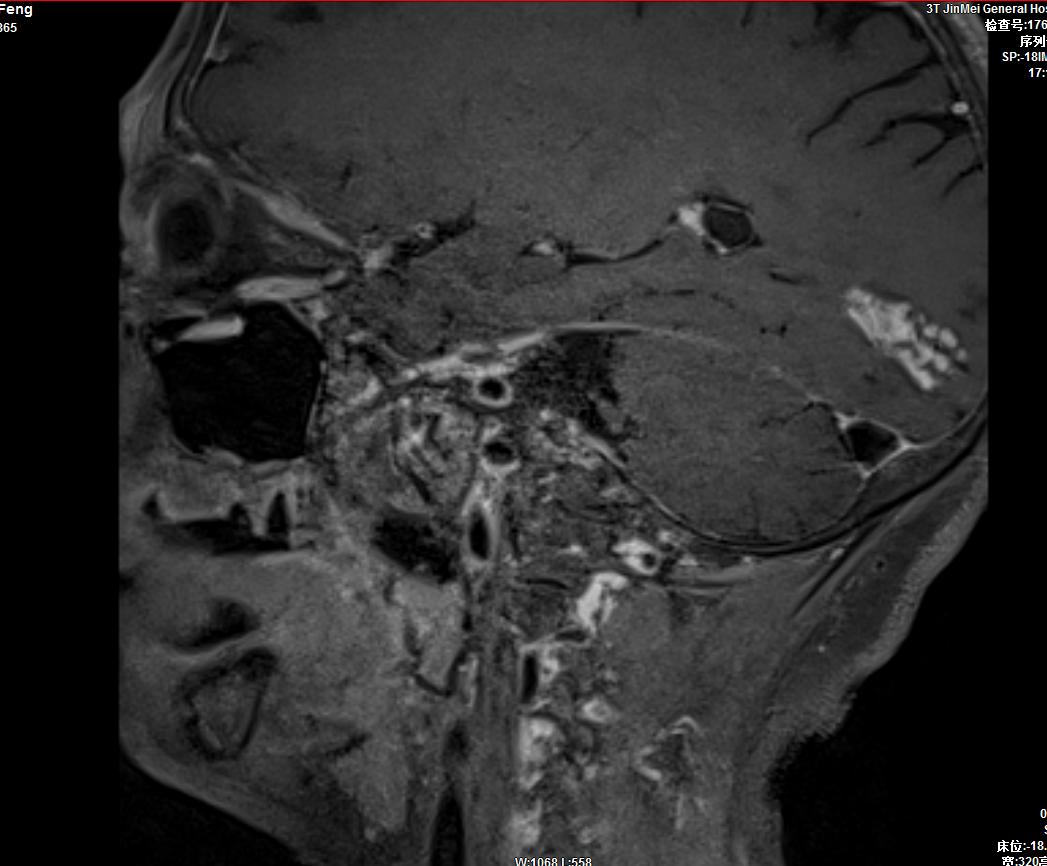

血管高分辨成像

4、明確動(dòng)脈狹窄原因,粥樣硬化斑塊的成分,指導(dǎo)臨床提早進(jìn)行干預(yù)。